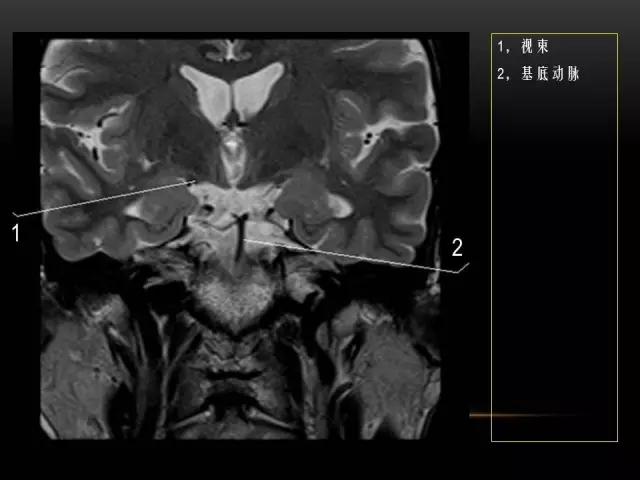

下文是在MRI下眼部及鼻窦的冠状位解剖图谱。